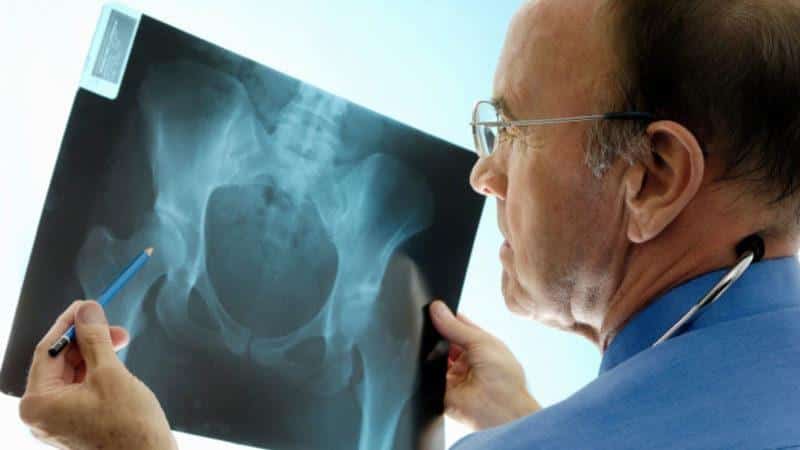

Для диагностики вывиха тазобедренного сустава требуется консультация специалиста. В ходе этой консультации будет проведен осмотр поврежденной конечности, после чего пациента направят на рентгенографию. Эта процедура необходима для точной классификации вывиха. Рентгеновский снимок позволит увидеть смещение тазобедренного сустава и степень его деформации, а также поможет установить характер травмы.

В самых серьезных случаях могут быть рекомендованы компьютерная томография или ангиографический рентген, которые помогут выявить возможные повреждения сосудов.